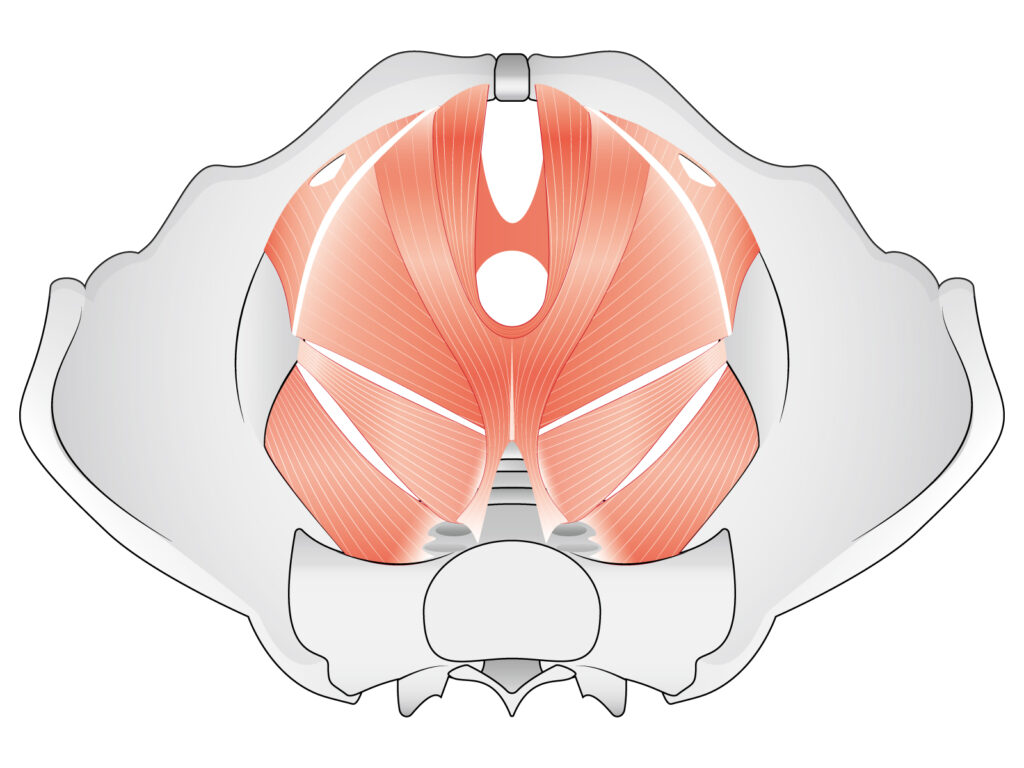

それは、身体の土台である「骨盤底筋群」へのアプローチにおいて、これほど画期的なものはないと確信したからです。

骨盤底筋群は、姿勢の安定、呼吸、内臓の保持、排泄機能など、生きるうえでベースとなる機能を支える重要な筋肉です。ここが機能低下を起こすと……